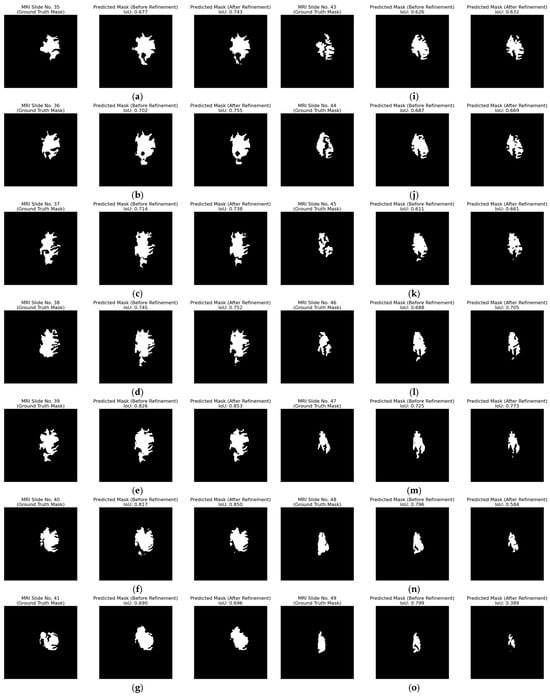

The strategy of removing ambiguous pixels that fall below a fixed percentage threshold and re-labelling them as background is evaluated on patient with ID “TCGA_DU_7010_19860307”. In Figure 17, the red curve, which shows the predicted overlap before refinement, sits well above the blue ground truth curve. After ambiguous-pixel removal with a threshold of 1.5%, the green curve moves between the other two, coming closer to ground truth. This positive result is also evident in most of the subfigures in Figure 18, where the IoU of the predicted mask after refinement is clearly improved. For example, in Figure 18a,b, the IoU increased from 0.677 to 0.743 and from 0.702 to 0.755, respectively.

Inter-slice WAO percentage after removing 1.5% of the most ambiguous pixels for patient with ID “TCGA_DU_7010_19860307”. The blue curve represents the white overlapping pixels of the ground truth masks, the red curve the predicted white overlapping pixels, while the green curve represents the refined predicted overlap by removing the ambiguous pixels with a 1.5% threshold.

Figure 18.

Qualitative evaluation of the refinement strategy by removing the ambiguous pixels with a 1.5% threshold on patient with ID “TCGA_DU_7010_19860307”. (a–q) Each triplet (left to right) displays the ground truth mask, the raw predicted mask, and the refined predicted mask for the top-performing segmentation model for MRI slices 35 to 51.

However, Figure 18p exposes an important failure case. An MRI slice with an initial low IoU of 0.594 contains a small tumor region that disappears completely when 1.5% of ambiguous pixels are set to background, producing an FN, which is the worst possible outcome in a clinical setting.

In order to avoid this issue and further improve the results of the post-heuristic refinement, we introduce an early-stop rule that limits refinement to the slices where it is helpful. The stopping point is found by locating the first sharp drop in the Gaussian-smoothed overlap curve. Figure 19 shows that, for this patient, the drop occurs at slide 46, thus creating an area of 12 slides (35 to 46) to which the refinement is applied.

Figure 19.

Inter-slice WAO percentage with early-stop window (MRI slides 35 to 46) after removing 1.5% of the most ambiguous pixels for patient with ID “TCGA_DU_7010_19860307”. The blue curve represents the white overlapping pixels of the ground truth masks, the red curve the predicted white overlapping pixels, while the green curve represents the refined predicted overlap by removing the ambiguous pixels with a 1.5% threshold.

The results of this effect are evident in Table 7. Refining every slice lowered the mean IoU (mIoU) from 0.799 to 0.761, but restricting refinement to the selected window raises IoU by almost 2%, giving a clear improvement for this patient.

Table 7.

Mean IoU (mIoU) for patient with ID “TCGA_DU_7010_19860307” at three stages: baseline, naïve 1.5% ambiguous-pixel removal applied to every slice (Raw Refinement), and the same removal restricted to the optimal window (slices 35–46).